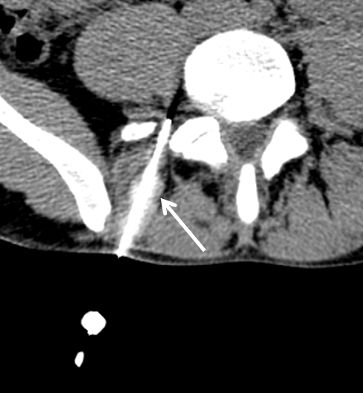

Infiltration

en radio ou sous scanner, découvrez les techniques radiologiques contre la douleur.